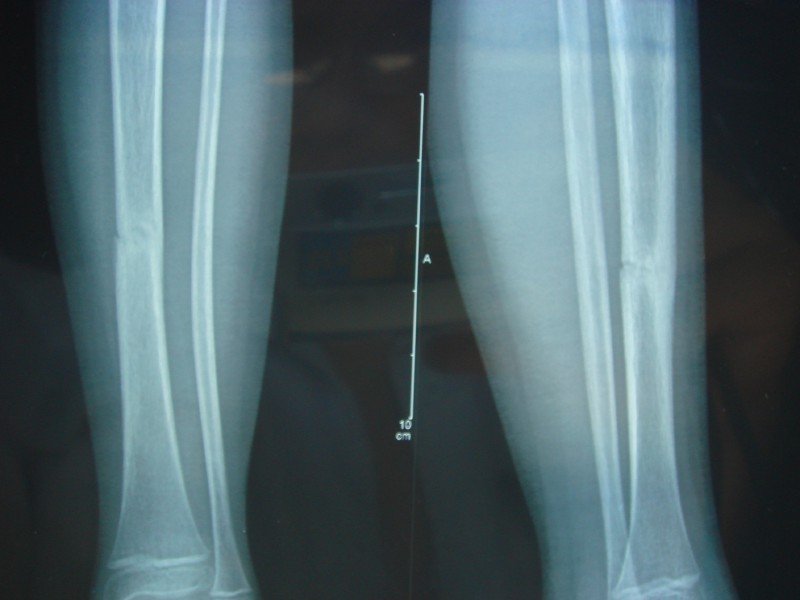

小孩6月10日出的车祸,小腿胫骨骨折,都70天了,8月20日复查还有缝,是不是对位不好啊 患者信息:女 6岁 江西 肇事司机要求先出院才能办理赔偿,这种情况能出院吗,小孩现在走路有点瘸,伤腿明显细一些,如果出院会不会有后遗症啊? 点击展开 匿名用户 2012-08-23 12:54 满意回答 6岁小孩,胫骨骨折2个多月,对位很好。小儿骨折愈合塑形能力夕匪厉强征厘,委快絮安好的现在已经骨痂形成很理想,不会有后遗症。 匿名用户 2012-08-23 15:45 宝宝知道提示您:回答为网友贡献,仅供参考。 相关问题 小孩7岁半,左小腿胫骨骨折,对线好,正位错位三分之一,用不用做手术 关于车祸导致右小腿大胫骨骨折,现在媳妇怀孕了,下一代会不会腿瘸 孩子今年9岁,四年前车祸小腿部粉碎性骨折,现今观察孩子脚有